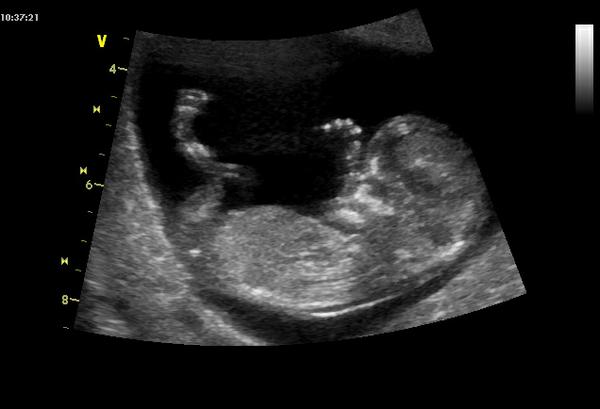

Holky dekuju 😉 Foto v albu 😉 Screening negativni a dr rikal, ze mame pekne miminko 😉 Podle PM jsem 12+5tt, ale CRL 13+1 tt. Merime 7cm 😉 Na pohlavi jsem se neptala. Byla jsem chvilku s mym Jirikem rozhozena..Mejdriv vse v pohode a pak prisla sestra s nejakym vypoctem a musel jeste neco zjistovat pres utz..Ze si to zadaji statistiky..Pak, ale rekl, ze je vse ok! 😀

@mishi Rekli jsme si o CD a doma nasli 8fotecek, tak 4 fotky v pohode. Doktor v pohode a se sestrou jsme se nasmaly 😉 Vysetreni jen ptes brisko 😉 Screening tech 1200 + 100 za fotky..

cau holky, vsechno dobry 😀 zaplatpanbuh (a to jsem neverici🙂 CRL 53,8, NT 2mm, srdce 164/min, rizika nizka, screening negativ.o den se lisi ultrazvukem od hulverta,

@kaijko my platili jen tu stovku, tak jsme jeste usetrili. divila jsem se, ale v mailu to maji nepresne napsane, ze to nelze pochopit, moje pojistovna to hradi